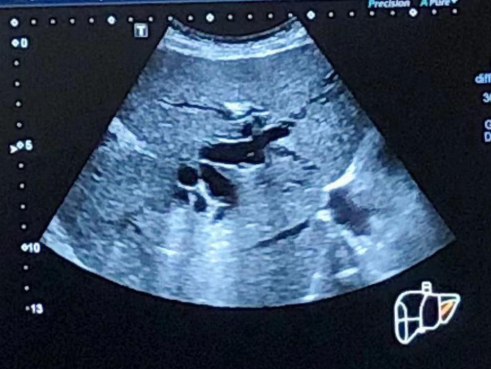

B超下扩张胆管

在做好充分的术前准备后,经过与患者及家属沟通,我院超声科团队在局麻下为患者行超声引导下行经皮经肝胆管穿刺置管引流术(PTCD)。在B超精准定位下经皮肝胆管穿刺成功,置管后引出胆汁,术后患者无明显不适,安返至病房进一步治疗和观察;次日李大爷黄疸、肝功能等情况逐渐得到缓解,精神状态明显好转,患者及家属对该手术治疗也感到很欣慰。